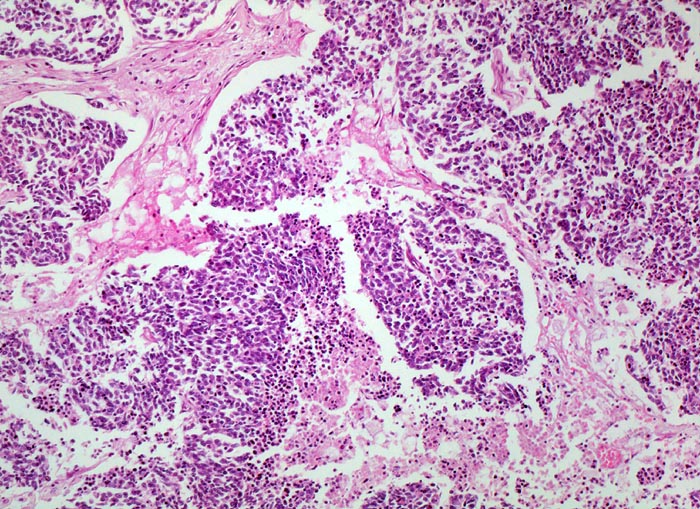

kleinzelliges Bronchuskarzinom: Tumornekrosen

Fokale Tumornekrosen.

Inoperables metastasierendes Bronchuskarzinom. Nikotinabusus 70 Packyears.

Histologie

100